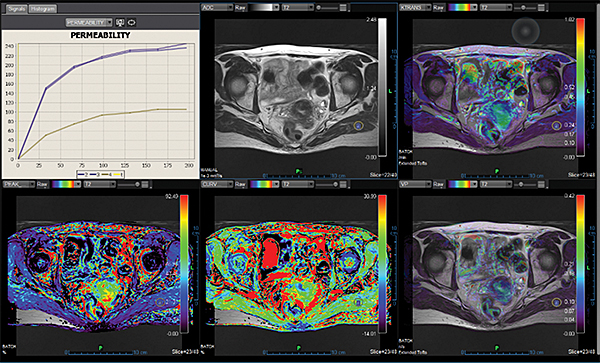

Додаток Prostate Streamlined.

Спеціальні програми Olea SphereTM для аналізу передміхурової залози включають в себе розширені можливості для оцінки дифузії та якісної оцінки перфузії. Також пропонують ефективний мультипараметричний аналіз усіх доступних послідовностей для візуалізації простати. В додатках реалізовано аналіз кінетики та кількісних даних на основі надійних математичних моделей. Програми передміхурової залози включають звіт PI-RADS® 2 для покращення виявлення, характеристики та вірогідності встановлення діагнозу раку простати. Цей програмний пакет стандартизує виклад протоколів опису, а також вказує рівень підозри або ризик виникнення клінічно значущих пухлин.